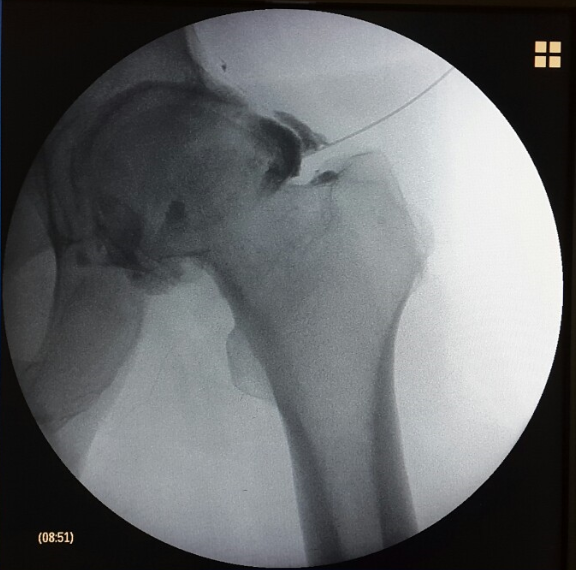

Ασθενής με οστικό οίδημα ισχίου

Ασθενής 67 ετών, με άλγος δεξιού ισχίου. Η μαγνητική έδειξε ότι υπάρχει οστεοαρθρίτιδα με οστικό οίδημα. Πραγματoποιήθηκε έγχυση ισχίου με υαλουρονικό και τοπικό αναισθητικό. Ο ασθενής ένιωσε άμεσα ανακούφιση που διατηρείται έως σήμερα 1.5 χρόνο μετά